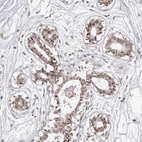

Immunohistochemical staining of human breast shows moderate nuclear positivity in glandular cells.